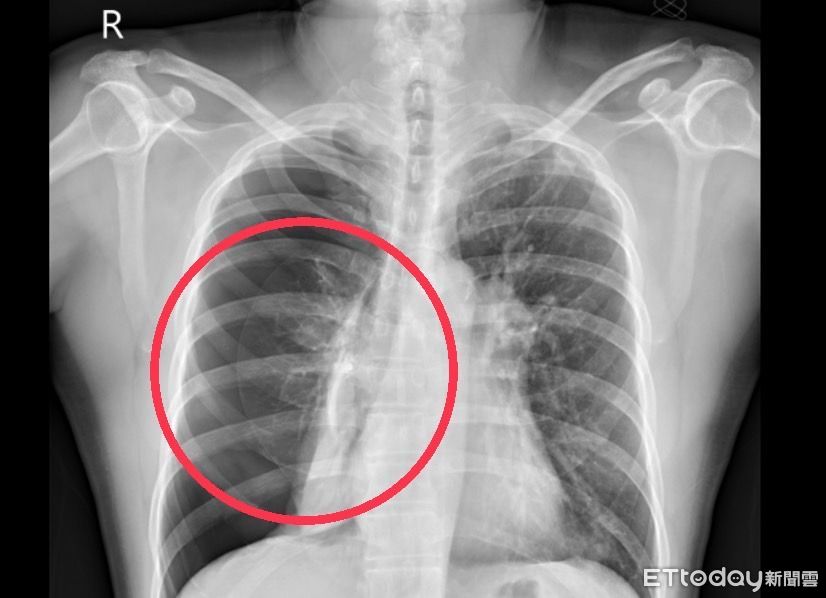

▲6旬男子午睡後突然呼吸困難,醫師籲抽菸者注意原發性氣胸,圖非當事人。(圖/衛福部南投醫院提供)

施志宏表示,自發性氣胸好發於高瘦年輕的男性,不過有抽菸習慣的中年民眾仍不能大意,如許姓男子就是20多年的老菸槍,提醒抽菸會增加肺部氣泡的形成和破裂的風險機率,建議應戒菸。

國軍台中總醫院胸腔外科主任謝志明表示,氣胸依病況輕重程度而有不同的治療方式,大致分為保守治療與積極治療:保守治療為氧氣給予、胸管引流,但復發率較高,而積極治療便是進行手術;許男在短短數日內便復發,未來再次復發的機率高,因此安排進行手術治療,目的是找出病灶並將其切除,再加上肋膜粘黏術,使肋膜腔完全粘黏,通常可控制復發率在3%以下,讓病患恢復正常的生活品質。